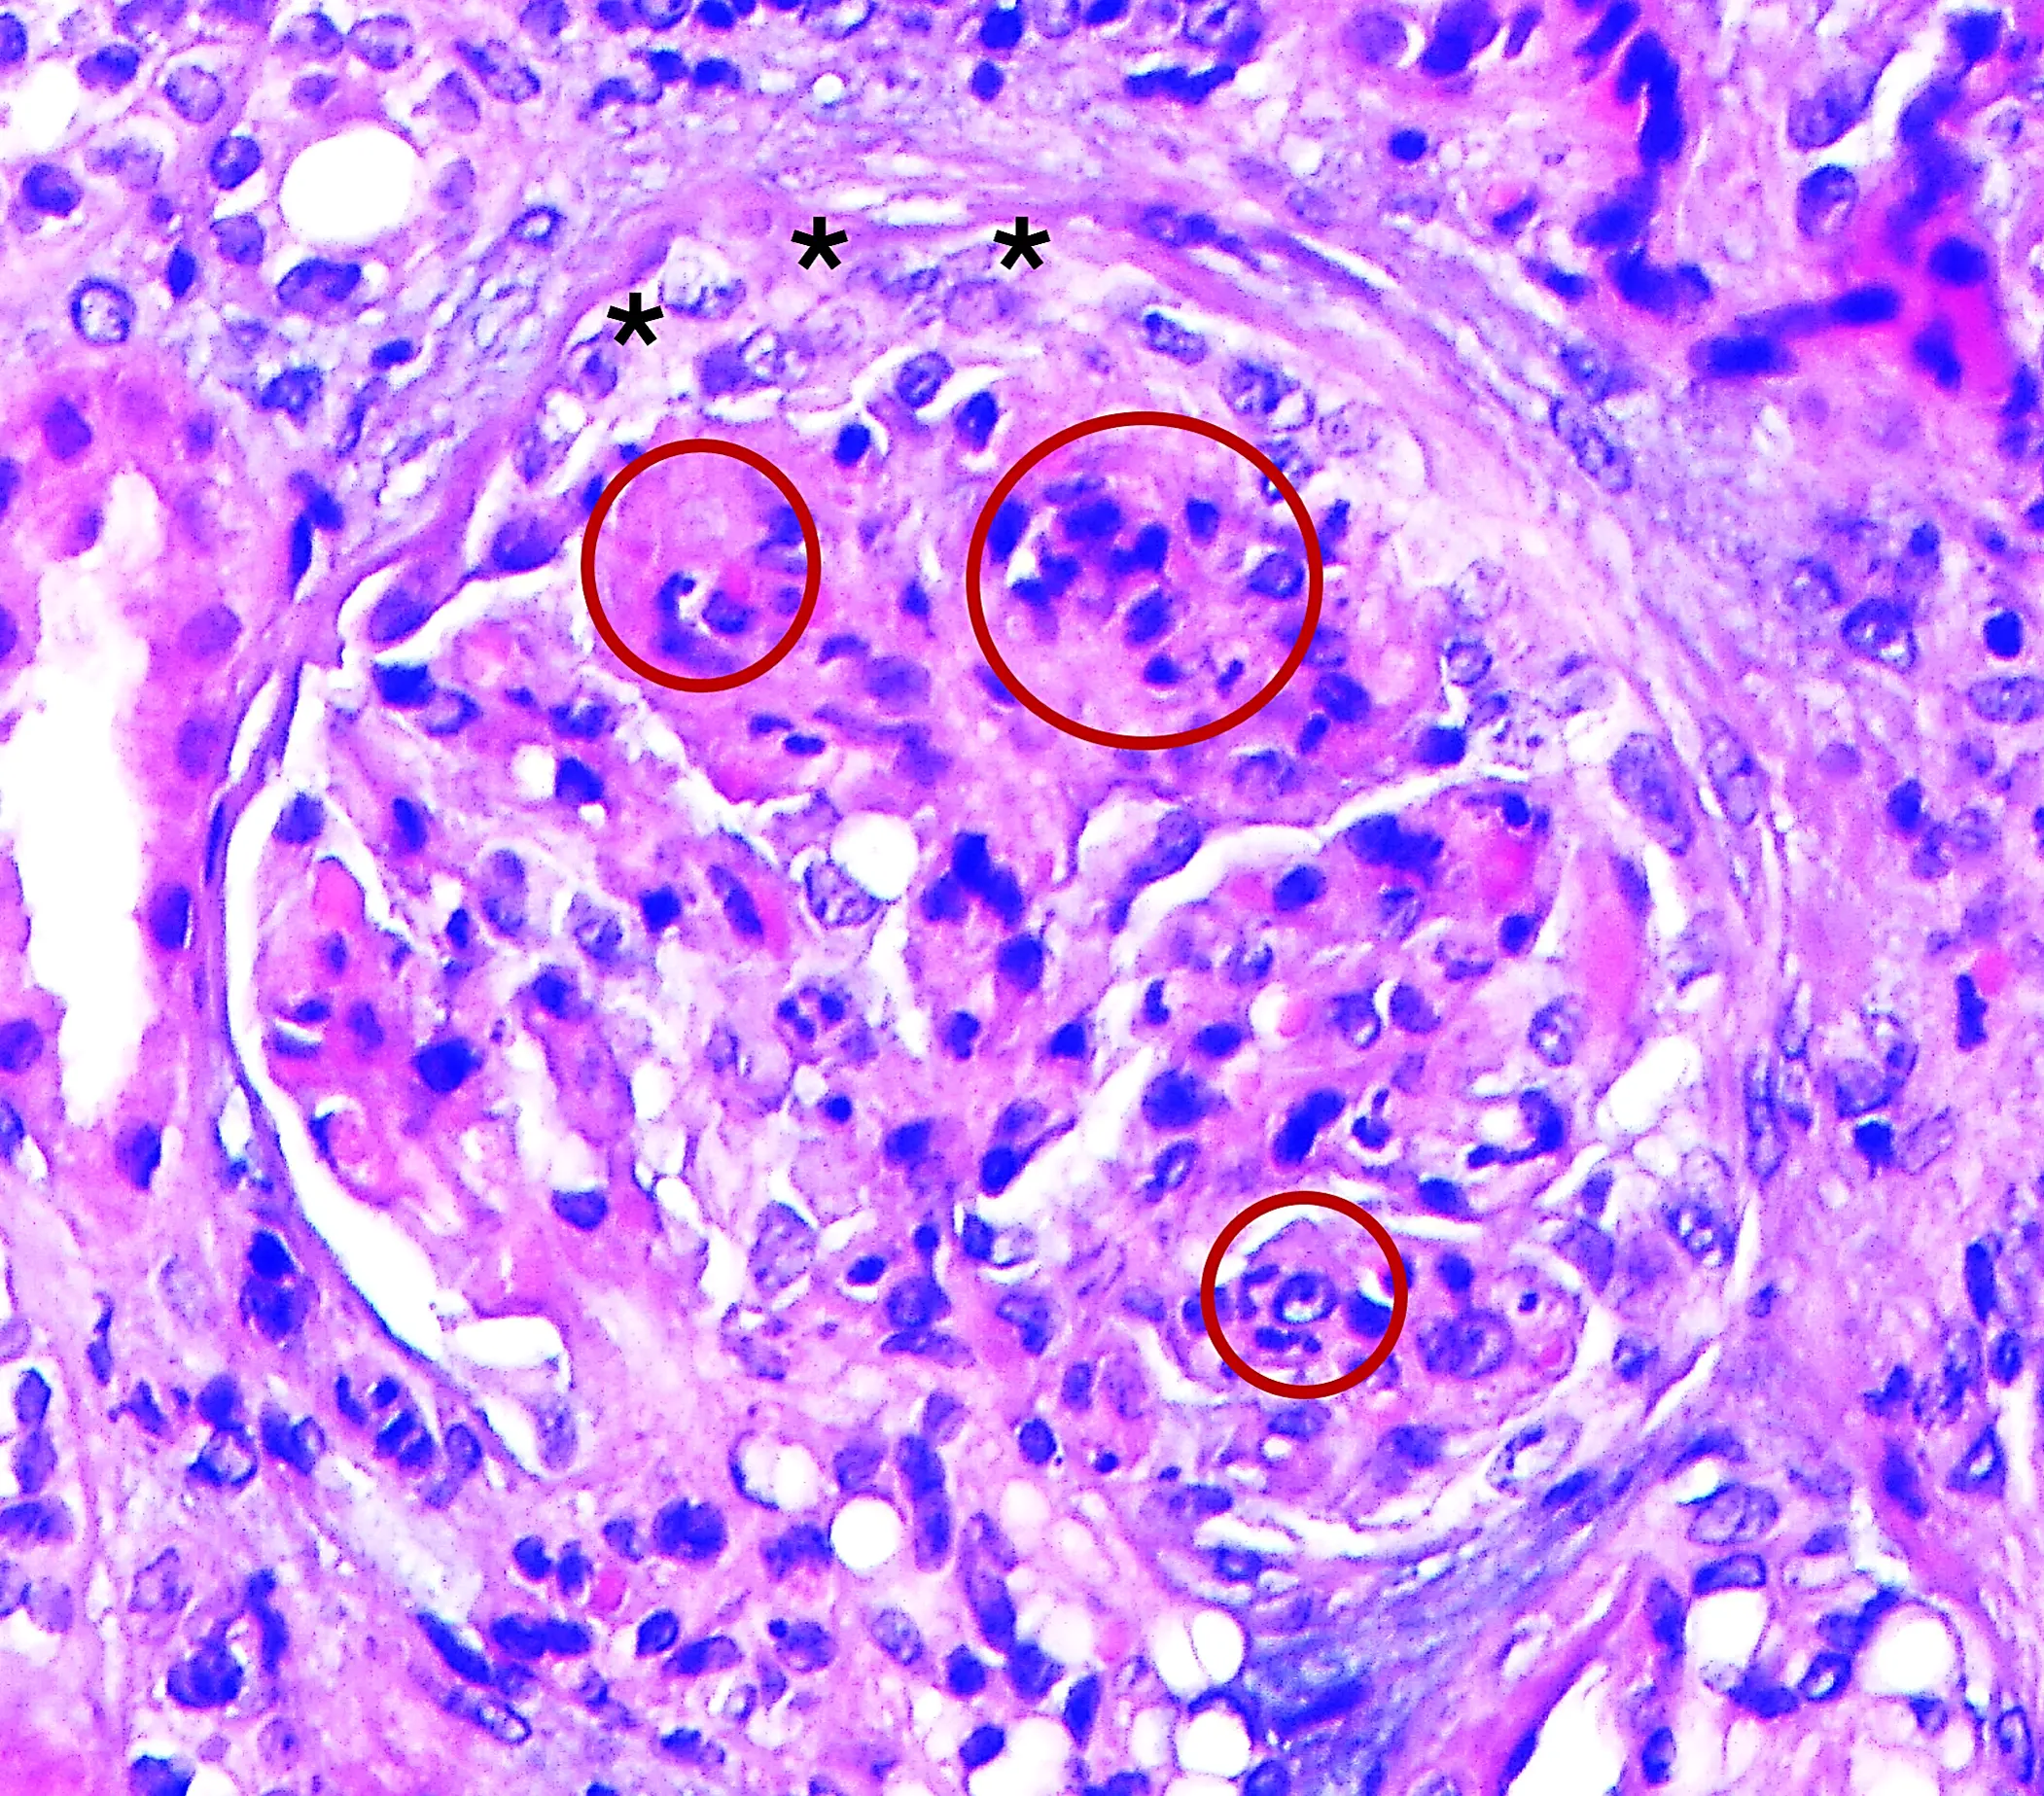

H&E con proliferación extracapilar fibrocelular en Glomerulopatía C3

Img. 6. H&E. Glomérulo con proliferación mesangial y endocapilar (O rojo). También se aprecia proliferación extracapilar fibrocelular (* rojo). 40x.